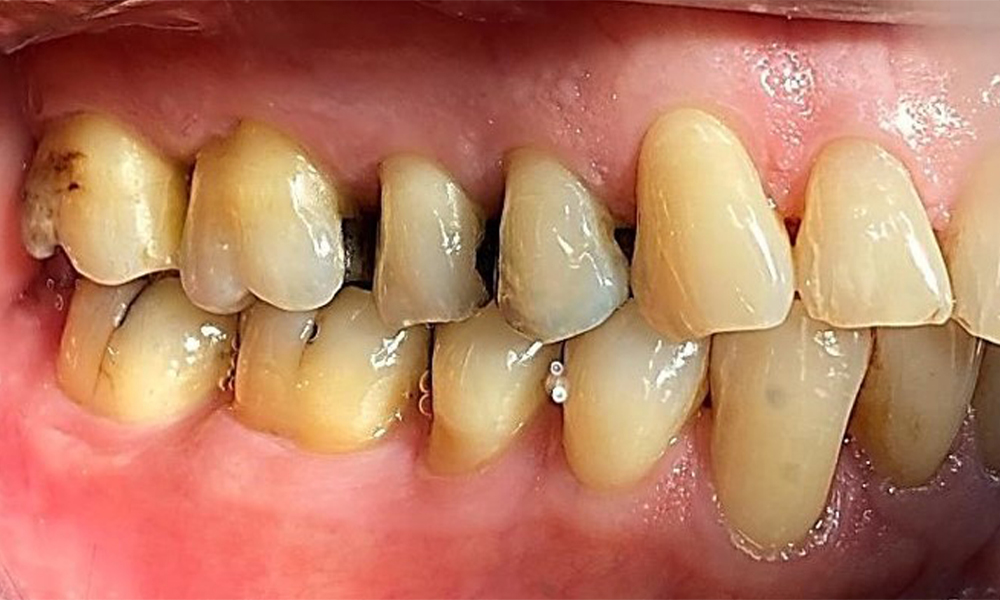

Пациентът има пълно съзъбие с 28 зъба, което включва амалгамни и композитни пломби в областта на моларите и премоларите. На зъб 14 има видима клинична маргинална празнина. Зъб 27 има адекватна златна инкрустация. Налице са и генерализирани атриции и абразии. (фиг. 2, фиг. 3, фиг. 4, фиг. 5, фиг. 6)

Пациентът е с пародонтит II стадий, степен В (5). Клиничните дълбочини на сондиране от 1 до 3 mm са във физиологичния диапазон. Локализирани дълбочини на сондиране от 5 mm са наблюдавани медиопалатинално на 17 и 27. Налице са генерализирани рецесии от 1 до 3 mm с частична загуба на интердентални папили (фиг. 2, фиг. 3, фиг. 4)